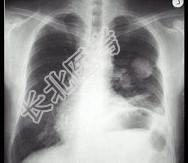

- 单项选择题男,67岁, 胸痛半个月,胸片检查如图, 最可能的诊断为 ( )

A、左上肺结核球

B、左上肺周围型肺癌

C、左上肺炎性假瘤

D、左上肺球形不张

E、左上肺脓肿